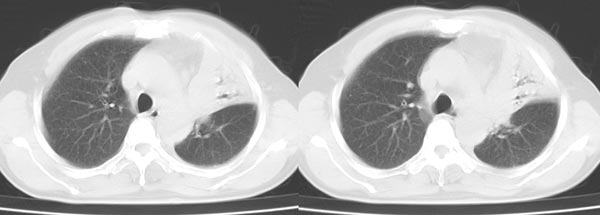

以下是引用dyqct在2006-4-1 22:20:00的发言:[br]左肺上叶明显萎陷、实变,支气管大部通畅,部分扩张,部分壁似见串珠状钙化。主动脉弓旁见肿大淋巴结。纵隔左移。左侧胸壁后缘见新月形高密度,边界清楚。[br] 考虑:1、左肺上叶肺不张伴支气管扩张(牵拉性),可能为支气管内膜结核所致。[br] 2、左侧少量胸腔积液。[br]

以下是引用piao001在2006-4-2 14:13:00的发言:[br]左肺上叶不全性不张,其内见钙化及扩张支气管,结合病史,考虑支气管内膜结核。建议支气管镜明确检查。